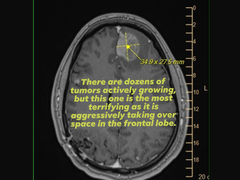

Como prova, ela também anexou uma imagem de um exame de ressonância magnética do cérebro que mostrava um tumor agressivo no lobo frontal, enquanto pedia apoio ou ajuda dos executivos da Epic Games, que tomaram as principais decisões sobre as demissões.